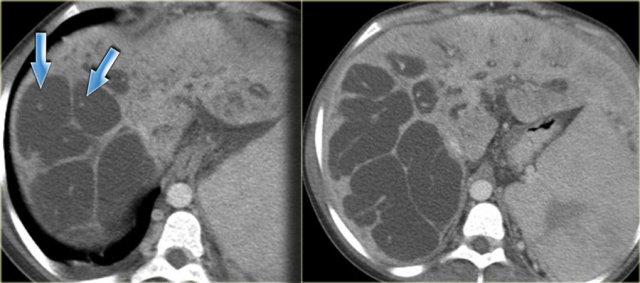

Bên trái là hình ảnh CT của cùng bệnh nhân.

Lưu ý dấu hiệu chấm trung tâm và tổn thương theo phân thùy.

Bệnh nhân này có xơ gan kèm lách to do tăng áp lực tĩnh mạch cửa.

Giãn ống mật ngoài gan hiện diện trong 53% các trường hợp, thứ phát do viêm đường mật và sự di chuyển của sỏi hoặc bùn mật.

Đây là các dấu hiệu thứ phát, không phải là một phần của bệnh nguyên phát.

Bên trái là hình ảnh bệnh nhân với các ống mật giãn kèm sỏi trong ống (mũi tên)

Các dấu hiệu bao gồm:

- Thận xốp tủy kèm hình thành sỏi (mũi tên đỏ)

- Giãn nhẹ ống mật (mũi tên xanh dương)

- Khối giảm tỷ trọng dạng tròn ở thùy gan phải

Khối ở thùy gan phải được xác định là áp xe.

Cần lưu ý rằng áp xe gan trong giai đoạn sớm có thể có hình ảnh khá đặc.

Trong chẩn đoán phân biệt, chúng ta cũng cần xem xét khả năng u tân sinh, vì bệnh nhân mắc bệnh Caroli có nguy cơ tăng cao phát triển ung thư biểu mô đường mật.

Cuối cùng, nếu có xơ hóa đáng kể và toàn bộ gan bị ảnh hưởng, những bệnh nhân này sẽ tiến triển thành xơ gan.

Bệnh nhân bên trái đã tiến triển suy gan nặng và được phẫu thuật cắt gan.

Lưu ý tình trạng giãn ống mật trong gan, lách to và giãn các tĩnh mạch bàng hệ.

Trên bệnh phẩm cắt bỏ có dấu hiệu chấm trung tâm (mũi tên xanh dương) và một ổ mủ nhỏ (mũi tên vàng).